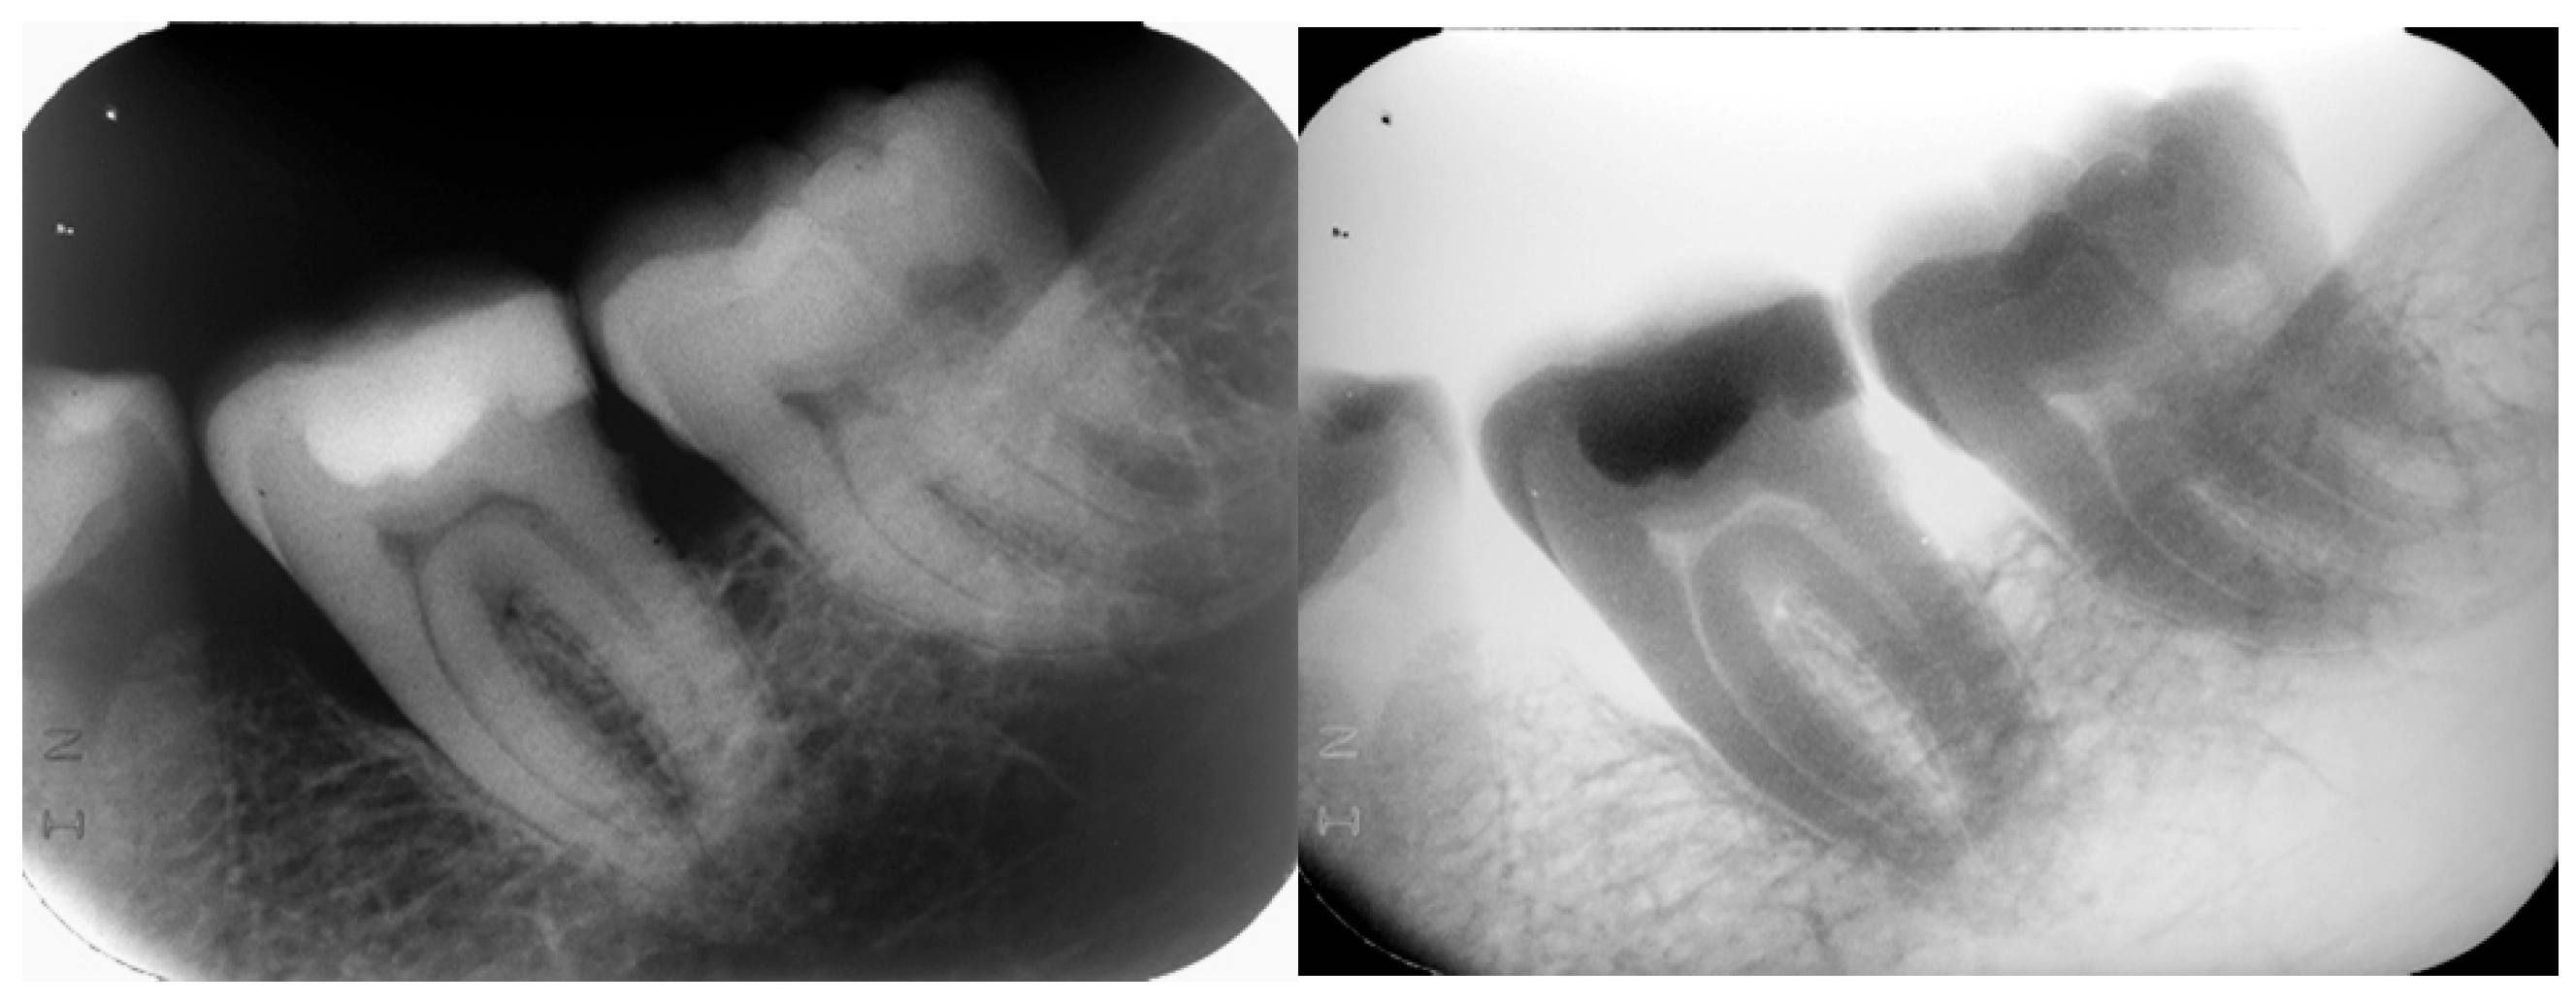

2.3. Radiologic Findings

The panoramic and intraoral radiographs revealed the internal structure of the atypical molar as well as the structure of neighboring teeth and anatomical features (Figure 4 and Figure 5). The intraoral radiographs were taken two months after the panoramic. There were no third molars in any of the quadrants. The atypical molar did not appear impacted and the surrounding cancellous bone exhibited a normal morphology, with no apparent pathologies. A mesial angular bone defect was identified in the proximal surface of the molar located distally of the second premolar, as well as a mild mesial tilting of this molar and an increased distance between its mesial root and the root of the second premolar. Horizontal bone loss was noticed between the two molars.

Figure 4.

Figure 5.

Intraoral periapical radiograph (original and reversed image).

The atypical molar had three distinct roots, directed parallel to each other and separated by normal interradicular bone: a mesial root, a distal root and a middle root. The mesial root was the longest and the distal the shortest (as depicted in the 2D image). All roots were slightly inclined distally. The periodontal ligament space and lamina dura of the molar roots were visible and within normal limits. Two pulp chambers (the mesial and the distal) and three root canals (each root had one root canal) were visible. The mesial pulp chamber extended to the mesial and middle root canals and the distal pulp chamber to the distal root canal. The crown of the molar appeared to be divided in two unequal halves by a vertical radiopaque thin zone extending from the occlusal surface—as a continuation of the occlusal enamel, also exhibiting enamel radiopacity—to the cervical area of the middle root.